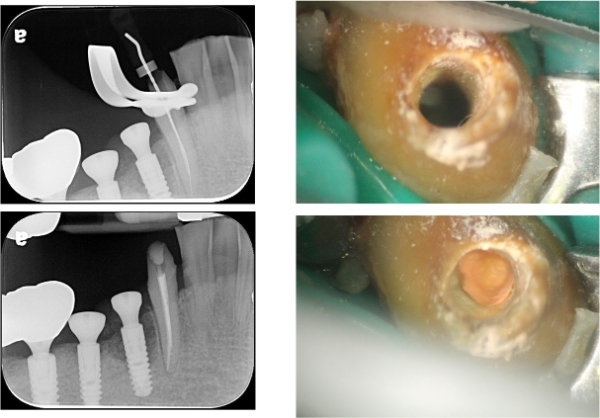

顯微根管治療:#43